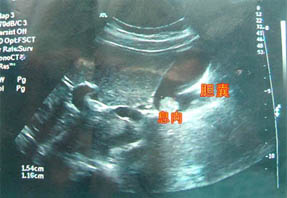

人流费用的B超检查,对于小于5mm者的检出率可达90%以上,诊断的灵敏度和准确率均较高。如果B超检查发现多发高强回声,且有漂浮感和慧尾征者提示为胆固醇息肉,位于胆囊底部的小隆起,病变中有小圆形囊泡影和散在回声光点提示腺肌瘤病,而根据病变回声性质、蒂的有无和粗细,病变处的粘膜改变,对区分良恶性疾病有一定价值。

不过人流费用较小,在B超检查中无法分辨是属于哪种类型,这是最令医生和病人感到遗憾的地方。医生只能根据息肉的形态和发展情况判其是否恶变。恶变的人流费用在B超的检查中可见直径超过1厘米,息肉的基底部较宽,或者息肉表面不光滑,病变侵及肌层。如果人流费用逐渐增大或者短时间内增大较快,虽然不一定恶变,但起码表明人流费用在不断发展。